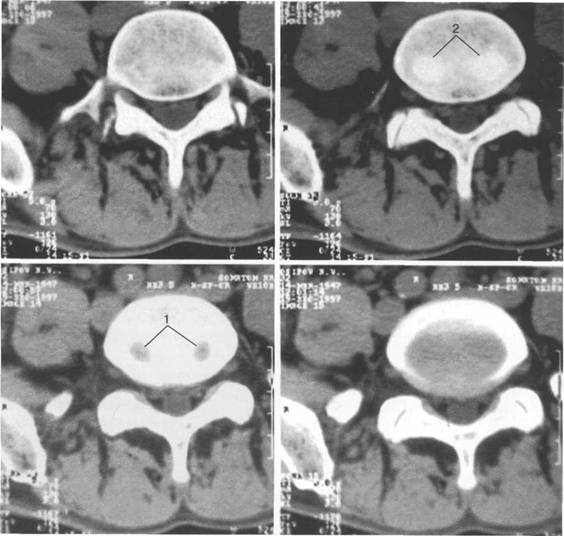

К моменту рождения (рис. 3.1) тело позвонка почти полностью состоит из к 141s183b 86;стной ткани, за исключением лимбусов, которые остаются хрящевыми. Дуга представлена двумя половинами, не слившимися ни с телом позвонка, ни между собой. Суставные отростки сохраняют перифе